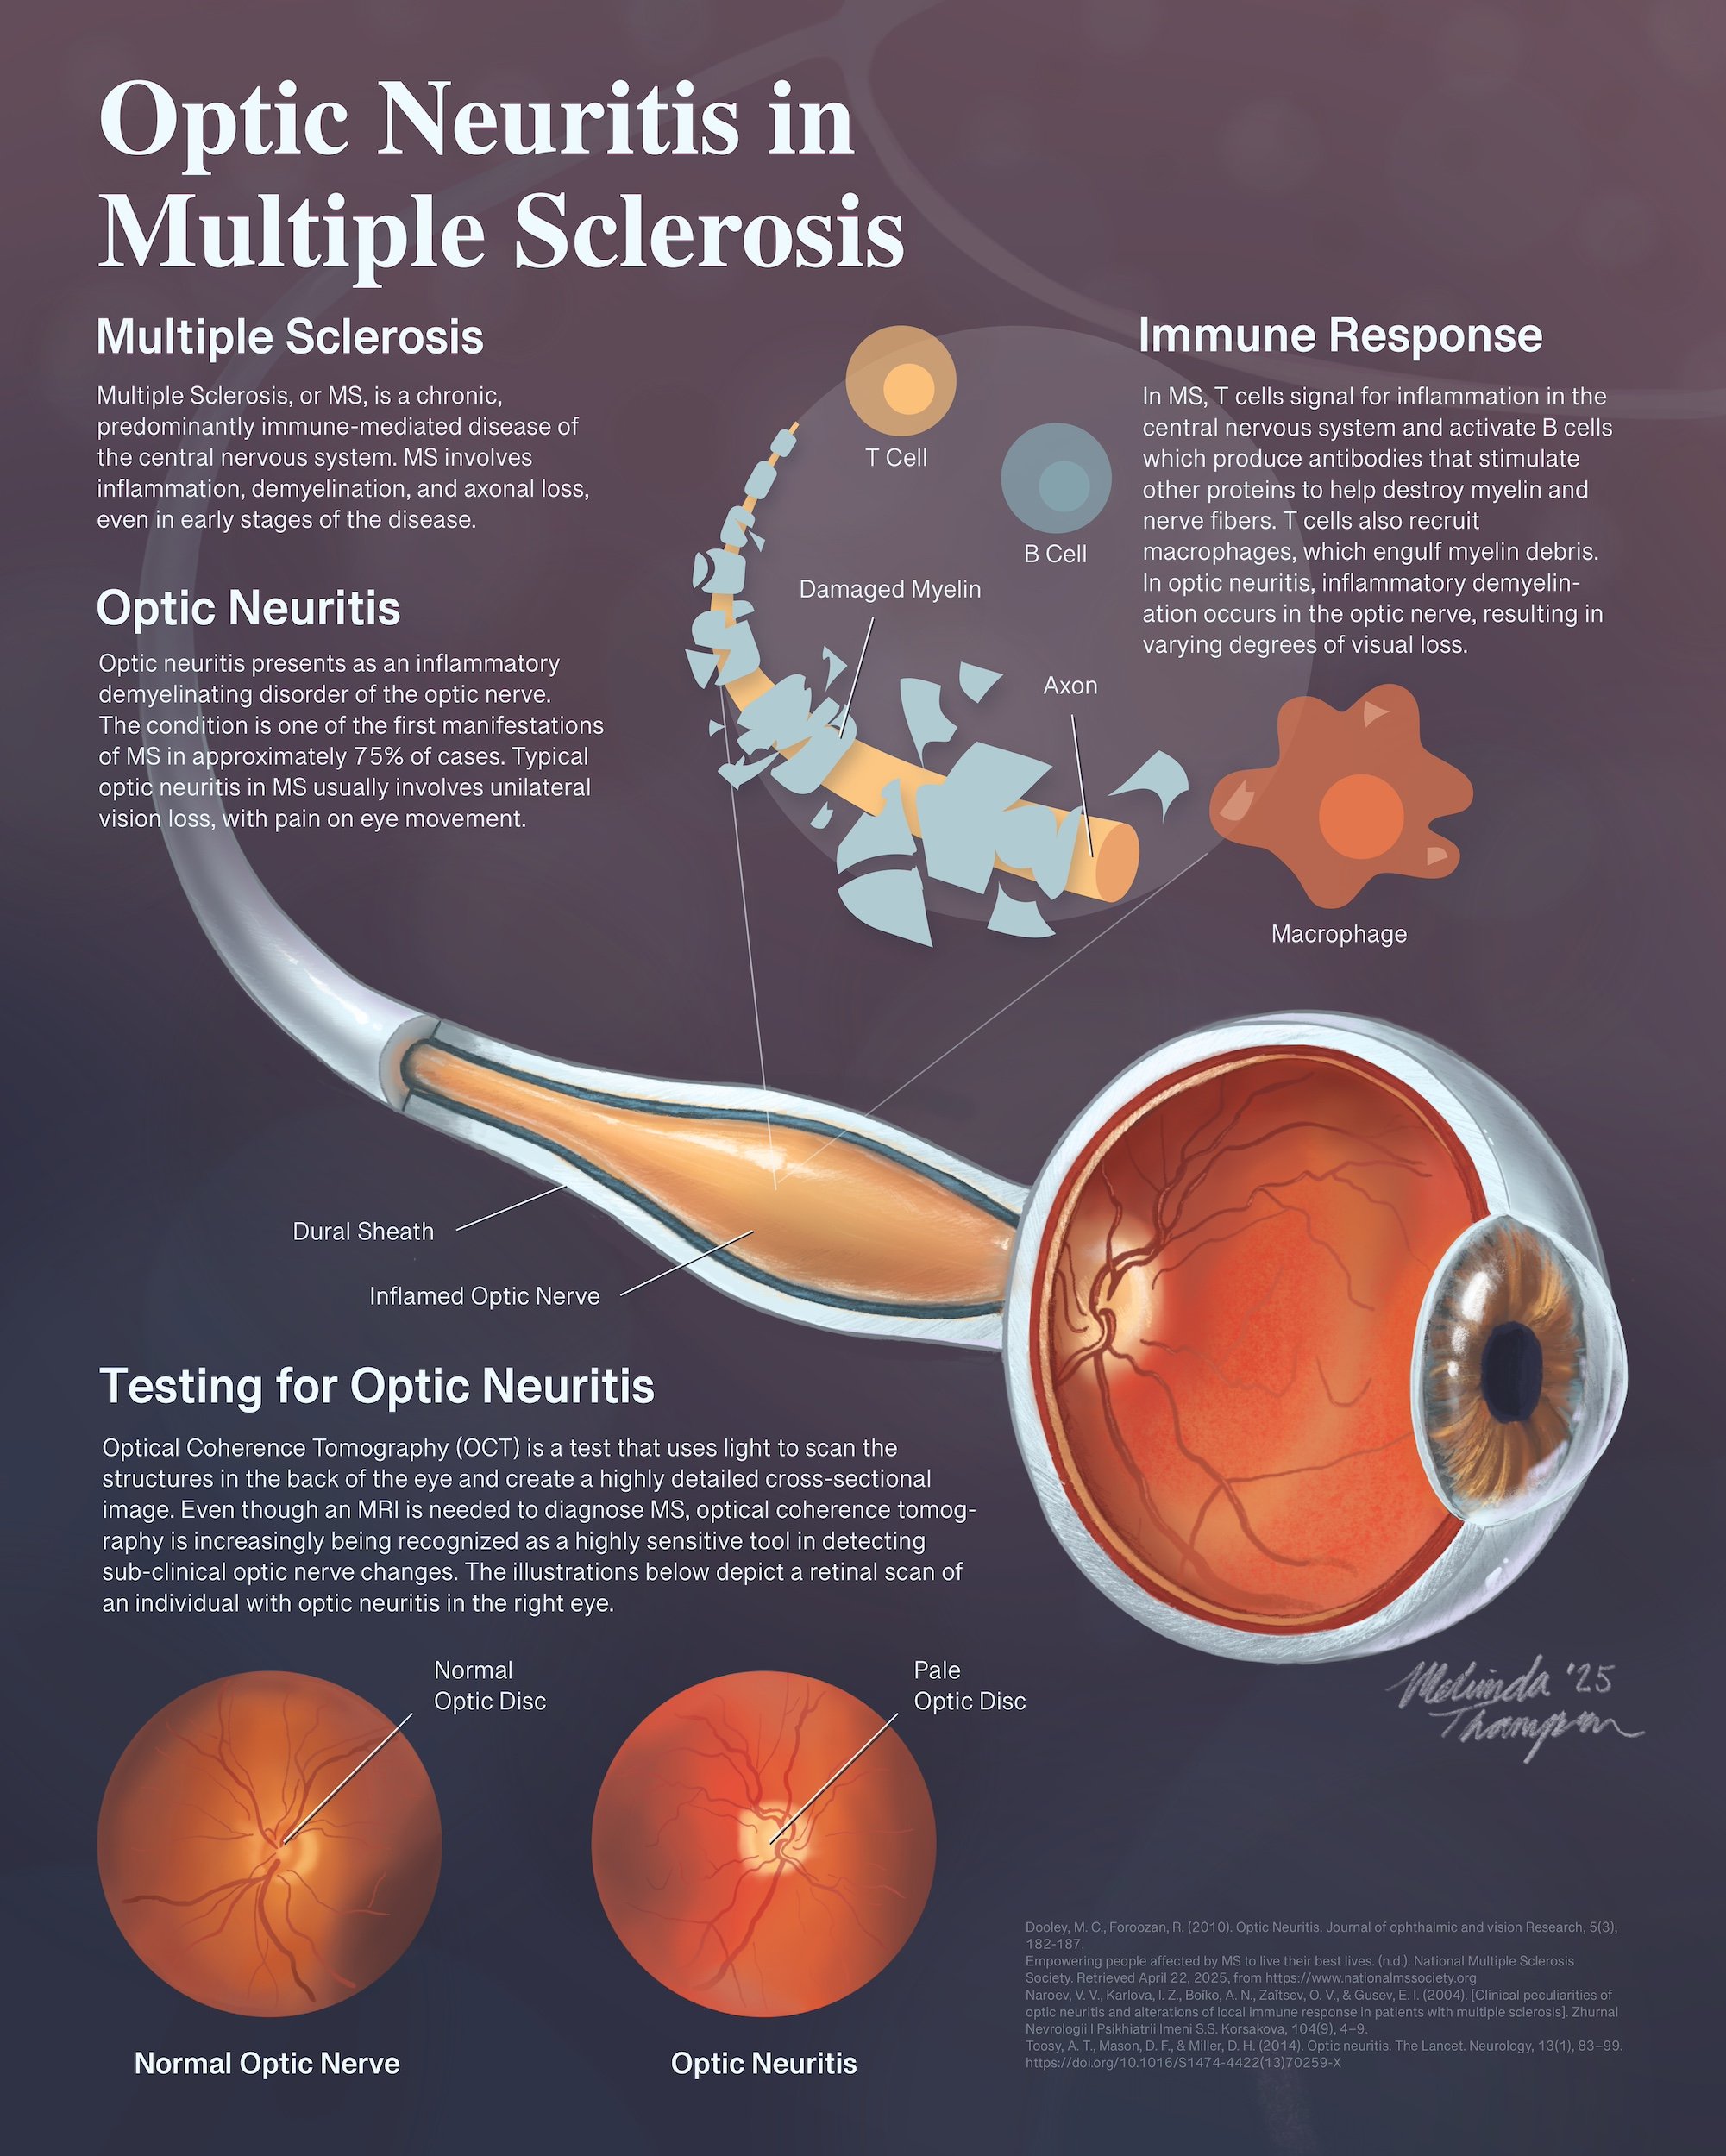

Pathophysiology poster: Optic Neuritis in Multiple Sclerosis